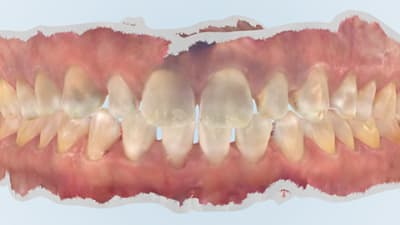

Case Report An Interdisciplinary Approach to Solving a Black Triangle Dilemma Andrew E. Skasko, DDS July 15, 2021 2 min read